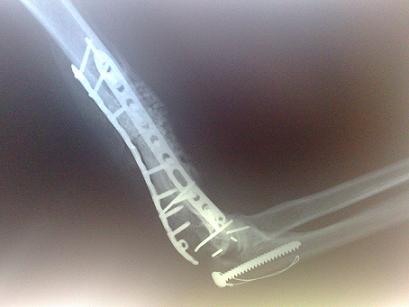

oui accident de moto en 2006, fraca du coude gauche, a l epoque j avais frolé l emputation!

et j ai subit il y a 3 semaine a paris cette opération par un super professeur, la sixième entre autres greffe de tendon d achile(prelevé sur donneur ) pour me faire un tendon tricipital

voici les radios après mes premières opérations